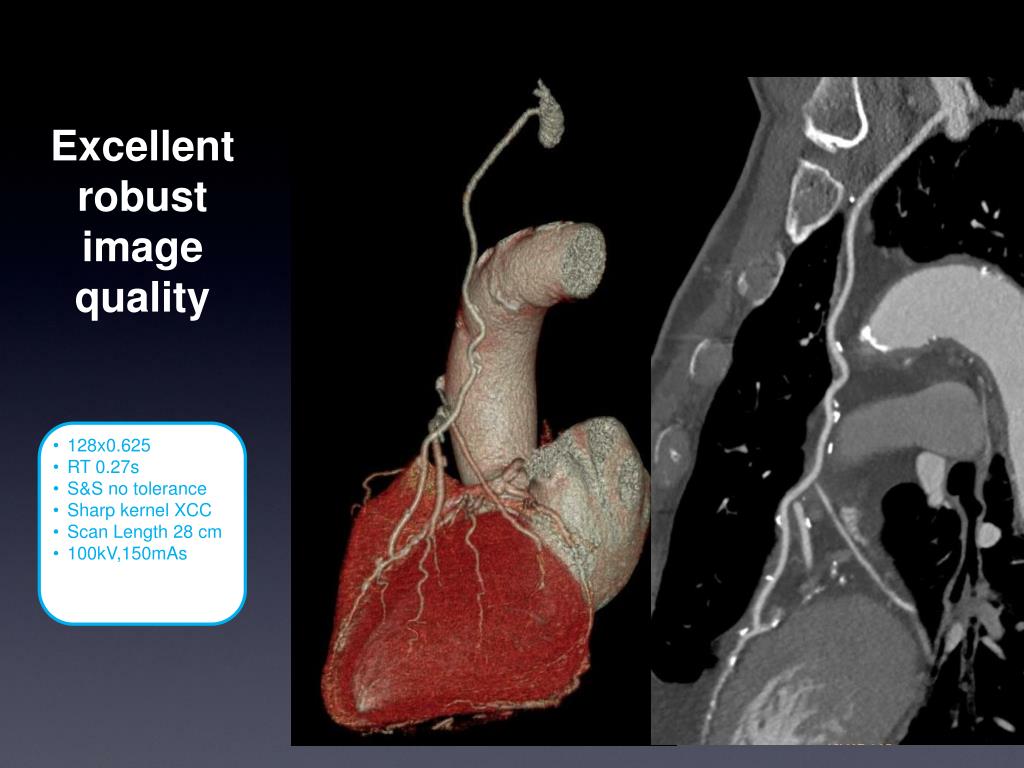

9. 128x0.625 • RT 0.27s • S&S no tolerance • Sharp kernel XCC • Scan Length 28 cm • 100kV,150mAs Excellent robust image quality